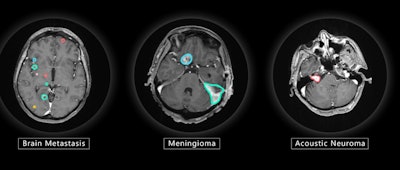

VBrain maps three types of brain tumors -- metastasis, meningioma, and acoustic neuroma -- allowing patients to begin radiation therapy more quickly than when contouring must be performed manually, the company said.

VBrain applies autocontouring to the three most common types of brain tumors: brain metastasis, meningioma, and acoustic neuroma. Image courtesy of Vysioneer.In an 18-month clinical trial conducted at the National Taiwan University Hospital in Taipei, researchers found that VBrain had a 12.2% higher sensitivity for detecting lesions compared with manual contouring, and it decreased treatment planning time by 30.8%, Vysioneer said.